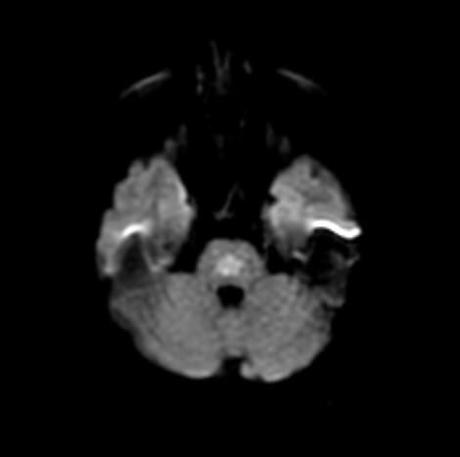

Cambios en la señal de los ganglios basales y la protuberancia, hiperintensas en Flair y con restricción en DW. Sugieren mielinolisis pontina o también llamado sind. De desmielinización osmótica, que buen caso, gracias por las imágenes

Cambios en la señal de los ganglios basales y la protuberancia, hiperintensas en Flair y con restricción en DW. Sugieren mielinolisis pontina o también llamado sind. De desmielinización osmótica, que buen caso, gracias por las imágenes

Síndrome de desmielinización osmótica con hallazgos pontinos y extrapontinos

Síndrome de desmielinización osmótica con hallazgos pontinos y extrapontinos

Mielinolisis pontina y extrapontina!

Mielinolisis pontina y extrapontina!